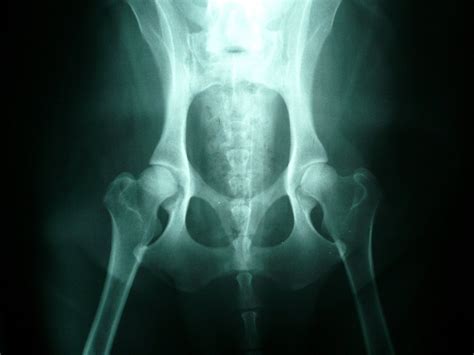

Dysplázia bedrového kĺbu

Dysplázia bedrového kĺbu u psa je dedičné ochorenie, pri ktorom sa bedrový kĺb nevyvíja správne. Namiesto hladkého pohybu sa kĺbová hlavica v jamke pohybuje neprirodzene, čo spôsobuje bolestivosť, zápal a postupné opotrebovanie chrupavky. Aj keď najviac postihuje veľké a rýchlo rastúce plemená, objaviť sa môže aj u menších plemien, vrátane Yorkshire teriérov.

Presná diagnostika zohráva esenciálnu úlohu pri riešení slabosti zadných končatín u psa. Veterinárna kontrola je rozdelená do viacerých etáp. Prvotným aktom je dôkladná veterinárna prehliadka. Počas nej sa dôsledne skúma kondícia zadných končatín a celkové fyzické zdravie pacienta. Nasleduje využitie zobrazovacích metód, ako sú röntgen a MRI. Neurologické testy môže veterinár priradiť, ak je to nevyhnutné. Majú za úlohu zistiť funkčnosť nervového systému.

Podľa diagnózy môže veterinár zvoliť farmakologickú liečbu, ktorá zahŕňa lieky proti bolesti a zápalu (analgetiká a nesteroidné antiflogistiká), prípadne lieky na podporu chrupavky a kĺbov. Pri závažnejších ochoreniach alebo úrazoch môže byť potrebné chirurgické riešenie, napríklad pri dysplázii bedrového kĺbu.